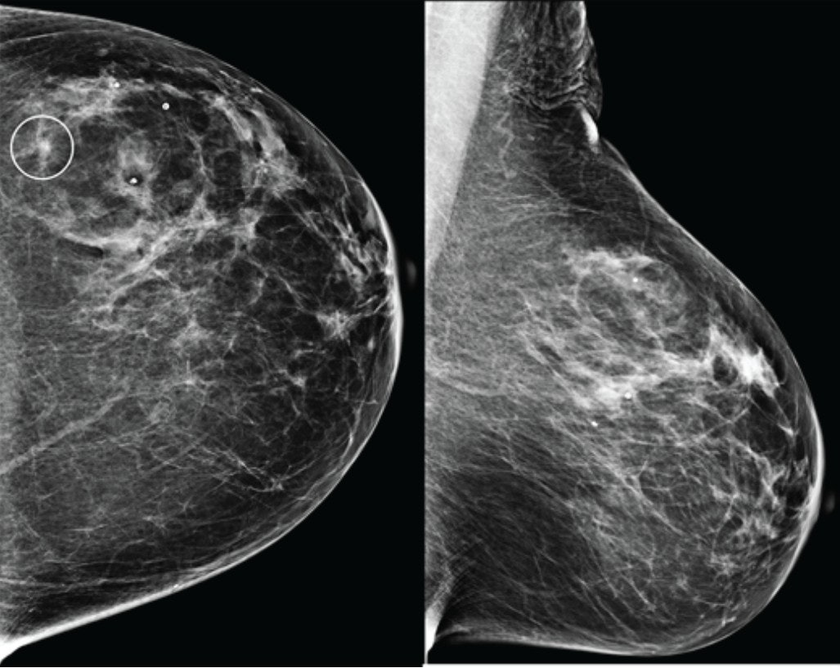

В конце августа 2025 года американский стартап Calidar представил инновационную систему 4D-маммографии, которая выводит точность диагностики злокачественных образований молочной железы на новый уровень. Эта платформа визуализации использует рентгеновскую дифракцию и искусственный интеллект для проведения исследования на молекулярном уровне.

Первая в своем роде система 4D-маммографии, разработанная компанией Calidar, позволяет решить существующие проблемы. Устройство измеряет, как рентгеновские лучи рассеиваются на молекулярном уровне: данный процесс известен как рентгеновская дифракция. Это создает уникальную структурную сигнатуру, которая отражает внутренний состав ткани молочной железы.Как построить цифровой фундамент для мебельного ритейла будущего

В отличие от традиционных рентгеновских снимков, которые основаны на форме и плотности, рентгеновская дифракция предоставляет дополнительную диагностическую информацию о том, из чего состоит ткань. Эти специфичные данные позволяют классифицировать раковые и доброкачественные образования с точностью, в четыре раза превышающей показатели традиционных систем визуализации.[1]